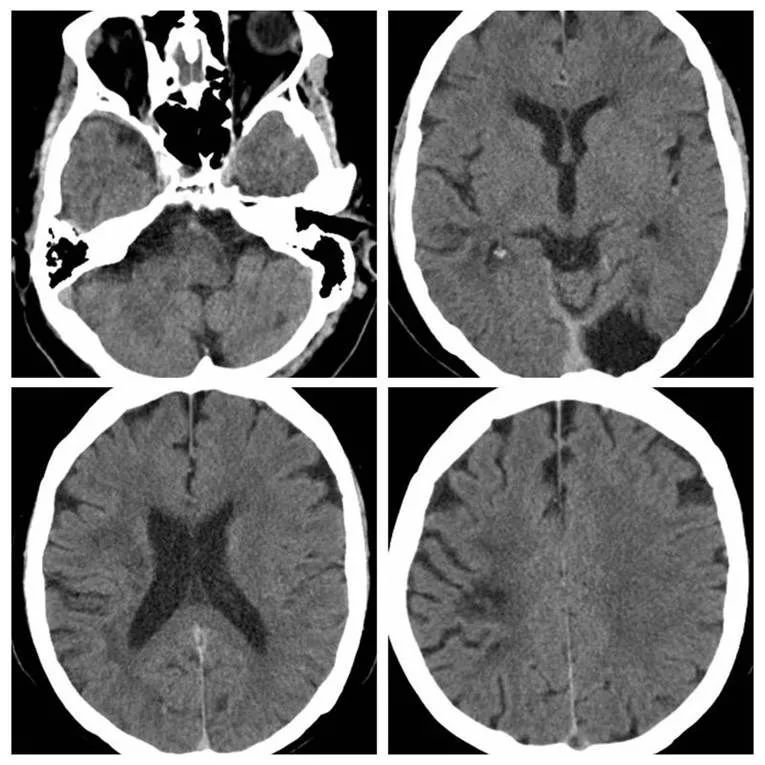

术后患者出现右颞部胀痛,查体同前,术后立即复查头CT未见出血(图15)。

图15

术后严格控制血压、镇静治疗,患者仍述头痛,分别于术后5小时及24小时复查CT,未见出血(图16,17)。

图16

图17

第二次复查CT后患者头痛逐渐缓解。